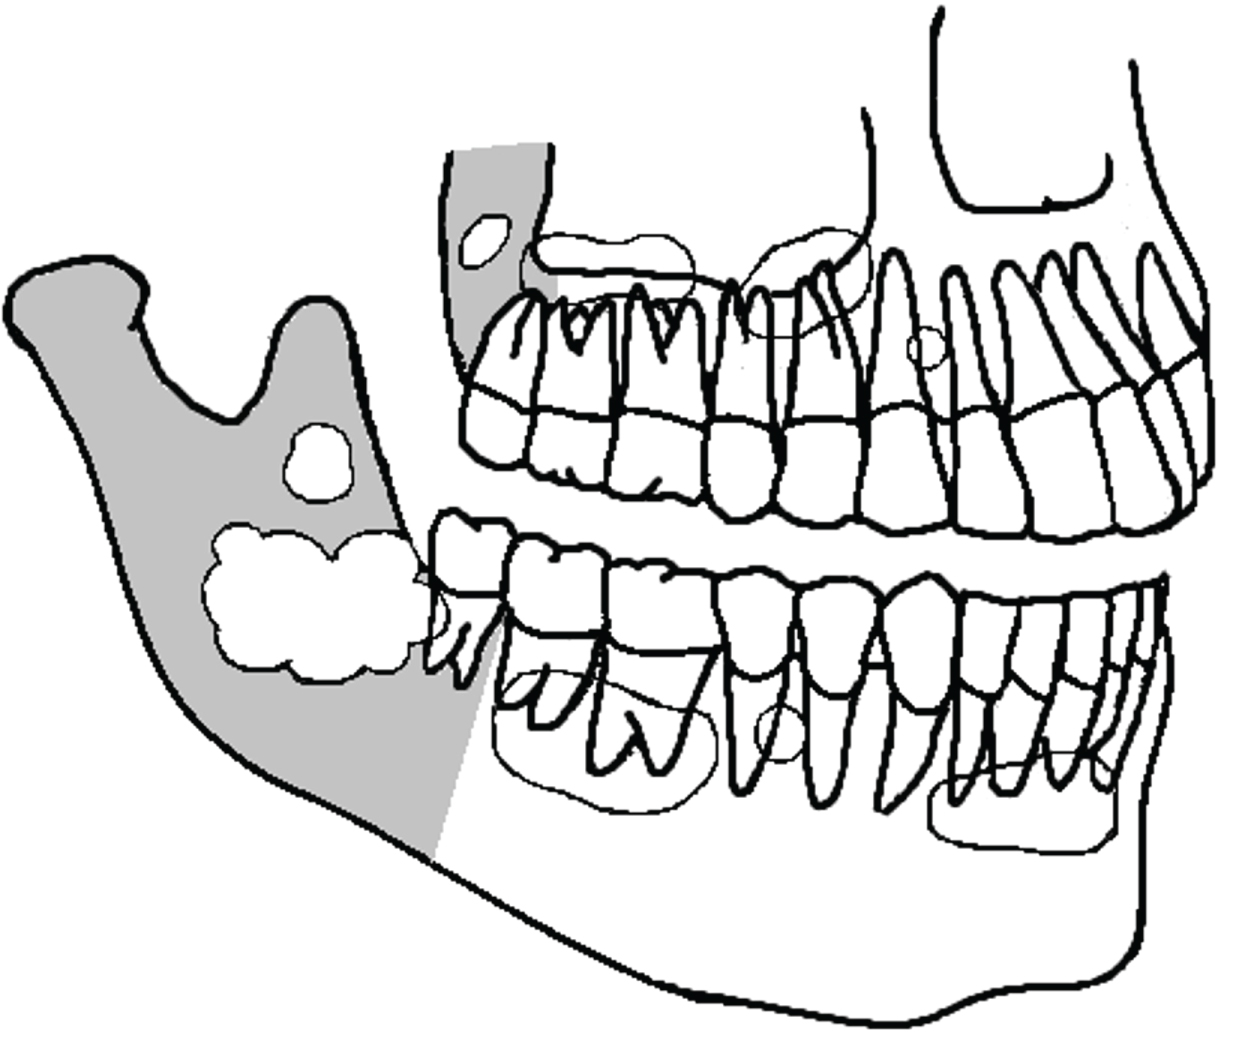

Radiographs of OKC's commonly present as unilocular cystic lesion with a well-defined border with or without scalloped margins but may also be multilocular. Frequently, they are not easily distinguishable from regular odontogenic cysts (Figure 4). OKC's may have no relation with a tooth or the crown may be completely inside the cyst. They may be positioned adjacent to the lateral aspect of the tooth root similar to a lateral periodontal cyst [18]. In a review of the radiographic aspects of 1138 OKC's, reported in several studies, including recurrent and syndromic OKC's, we found that 672 were unilocular (59%), 342 multilocular (30%), 202 had a smooth or well-defined border (18%), while 70 had a scalloped border (6%) [18,27-45]. In many instances, the radiological aspect was not reported.

Figure 4: Some of the several possibilities of OKC's presentation in the mandible and maxilla (schematic drawing). They are usually confounded with regular odontogenic cysts. Gray area is the posterior region of the jawbones. View Figure 4

Computed tomography is a valuable tool in detecting all dimensions of the OKC with a better definition of anatomical structures such as the inferior alveolar nerve (IAN), maxillary sinus, nasal cavity etc. CT-scans allow the precise detection of the cortical perforation (especially in the angle/ramus of the mandible or in the maxillary tuberosity), if present. The cortical perforation is probably the area where the overlying oral mucosa is attached to the OKC and such region must be included in the surgical excision. Smaller unilocular cysts, especially in the tooth bearing area, may be easily confounded with regular odontogenic cysts, specially the periodontal lateral cyst.